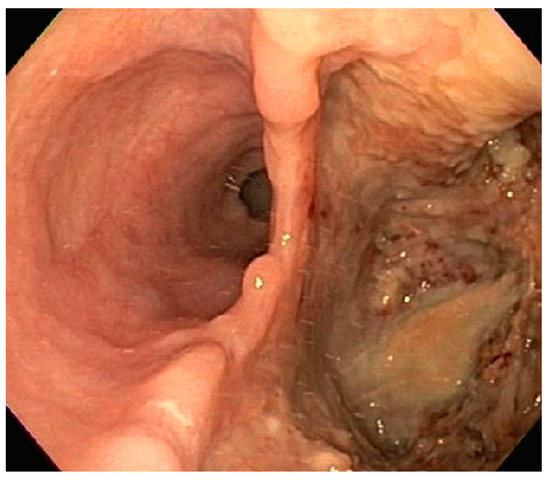

| 1 | F | 66 | Skin | Fundus, cardia, and body | Polypoid lesions with superficial ulcers | Esophagus, duodenum, mediastinum, cervical soft tissue, pancreas | Metastatic malignant melanoma | Radiotherapy and immunotherapy | Comfort care and death 5 days after EGD diagnosis of metastasis |

| 2 | M | 84 | Lymphoid | Fundus and cardia | Ulcerated and necrotic mass | Liver, urinary bladder | Diffuse large B-cell lymphoma | None | Death in 2 months after EGD diagnosis of metastasis |

| 3 | F | 35 | Lung | Fundus | Fungating mass | Esophagus, mediastinum | Large-cell neuroendocrine carcinoma | Chemotherapy-carboplatin/ etoposide | Death 1 month after EGD diagnosis of metastasis |

| 4 | F | 73 | Kidney | Fundus and body | Multiple large friable masses | Liver and lungs | Clear cell renal carcinoma | Nephrectomy, chemotherapy, immunotherapy (Axitinib) | Death 10 days after EGD diagnosis of metastasis |

| 5 | M | 76 | Lung | Body | Cratered ulcers | Liver, bone and adrenals | Small cell carcinoma (poorly differentiated neuroendocrine Ca) | None | Death 7 days after EGD diagnosis of metastasis |

| 6 | M | 61 | Lymphoid | Unknown | Clean based ulcer | None | Marginal zone lymphoma | Rituximab, Zanubrutinib, umbrasilib. OCHOP regimen currently | Progressive disease per latest scans despite therapy |